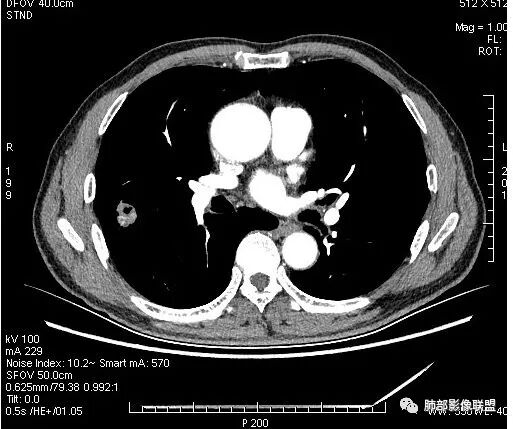

4.病灶轻到中度强化。病灶内血管走行较完好,病灶旁血管局部显示粗大。

病灶内“旁若无人”的血管走形也让人难以理解。而该疑问也存在于结核病灶的辨析当中。